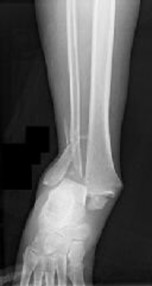

Figures 1 and 2 are the radiographs of a 68-year-old woman who comes to the emergency department after stepping into a hole and twisting her ankle. She is complaining of isolated ankle pain and is unable to bear weight.

After closed manipulative reduction and splint placement, she is scheduled for operative treatment. The stability of the syndesmosis should be evaluated after

How is syndesmotic instability best assessed intra-operatively?

How is syndesmotic reduction best assessed intra-operatively?

Our understanding of malreduction of the syndesmosis has changed over the years based on changes in technique and imaging. Our current understanding is that malreduction of the syndesmosis

Anatomic reduction and stabilization of the posterior malleolus fracture component

What is the morphology of the posterior malleolar fracture component?